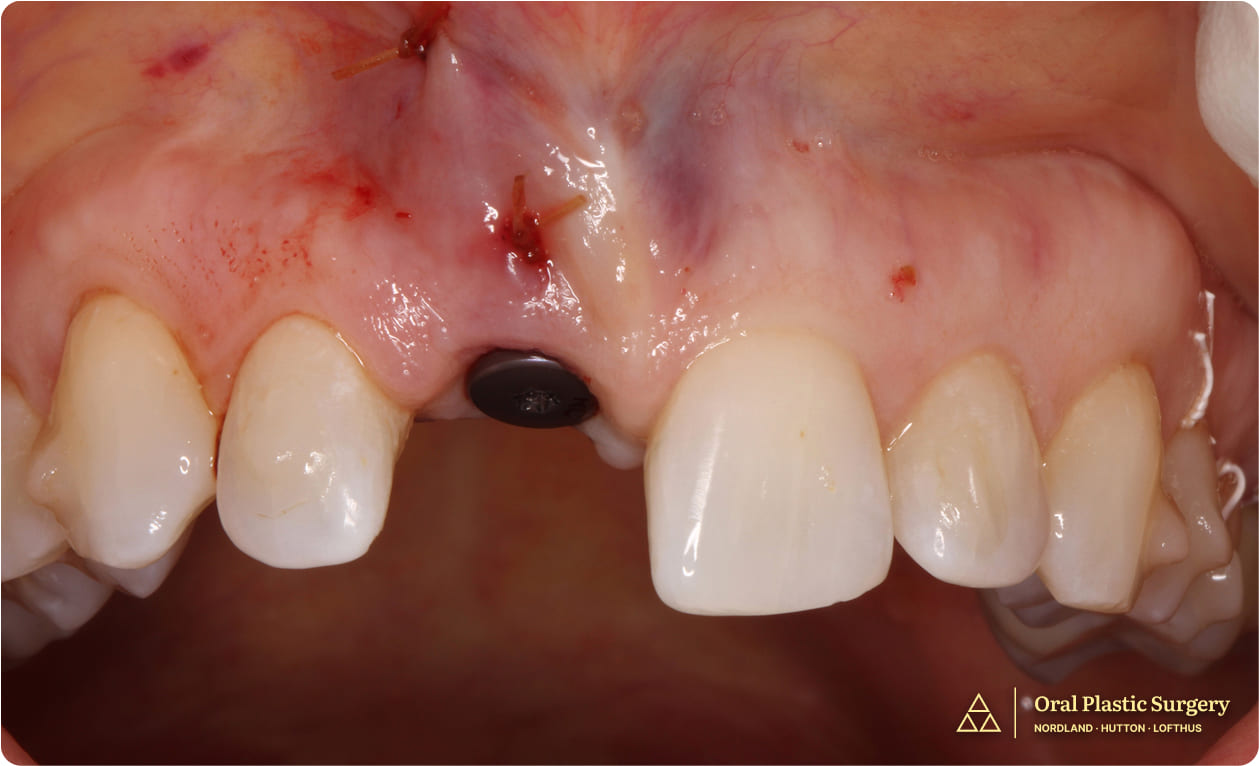

Stage 2: Implant Placement

After healing, the site was re-accessed, the fixation screw was removed, and the implant was placed into an ideal position for long-term stability and esthetics.

Implant positioning in the anterior maxilla requires extreme precision. The implant must be placed not only in the center of the available bone, but also in a position that allows the final crown to emerge naturally from the tissue, match the adjacent tooth contours, and support long-term papillae (the gum tissue between teeth).

Even a millimeter of deviation can result in visible esthetic compromise.

Following six months of bone block graft integration, the implant was positioned in the augmented ridge with ideal three-dimensional placement for long-term esthetic and functional success.